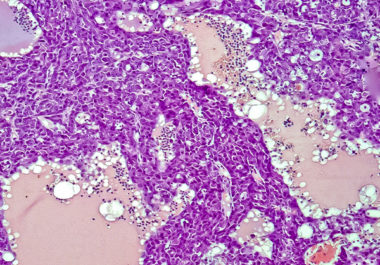

The FDA approved a combination of an immunotherapy and a therapeutic that can stop tumors from growing blood vessels for certain patients with liver cancer.

The FDA approved using a combination of nivolumab and ipilimumab, two immune checkpoint inhibitors, to treat certain patients with hepatocellular carcinoma.

The FDA expanded the use of the immunotherapy pembrolizumab to include the treatment of certain patients with liver cancer.